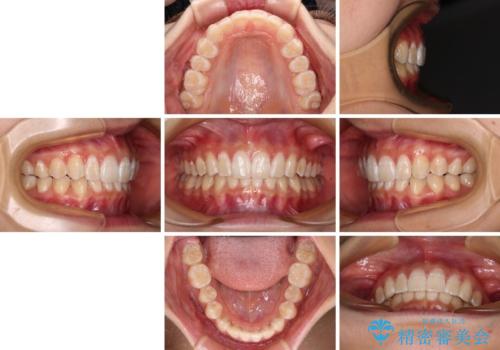

深い咬み合わせで前方に煽られた前歯 高校生のインビザライン矯正治療

インビザラインをしっかりと装着したことはもちろん、高校生は歯の動きが早いため、非常に短期間で治療を終えることができました。